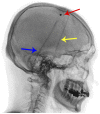

Purpose of review: This article provides neurologists with a pragmatic approach to the diagnosis and treatment of idiopathic normal pressure hydrocephalus (iNPH), including an overview of: (1) key symptoms and examination and radiologic findings; (2) use of appropriate tests to determine the patient's likelihood of shunt responsiveness; (3) appropriate referral to tertiary centers with expertise in complex iNPH; and (4) the contribution of neurologists to the care of patients with iNPH following shunt surgery.

Recent findings: The prevalence of iNPH is higher than previously estimated; however, only a fraction of persons with the disorder receive shunt surgery. iNPH should be considered as a diagnosis for patients with unexplained symmetric gait disturbance, a frontal-subcortical pattern of cognitive impairment, and urinary urge incontinence, whose MRI scans show enlarged ventricles and whose comorbidities are not sufficient to explain their symptoms. Physiologically based tests, such as the tap test (large-volume lumbar puncture) or temporary spinal catheter insertion for external lumbar drainage with gait testing before and after CSF removal, or CSF infusion testing for measurement of CSF outflow resistance, can reliably identify patients who are likely to respond to shunt surgery. Properly selected patients have an 80% to 90% chance of responding to shunt surgery, and all symptoms can improve following shunt surgery. Longitudinal care involves investigating the differential diagnosis of any symptoms that either fail to respond to shunt surgery or that worsen after initial improvement from shunt surgery.